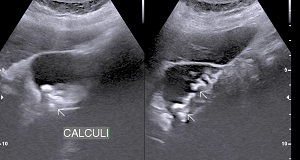

• Solitary Calculi:

• Multiple Calculi